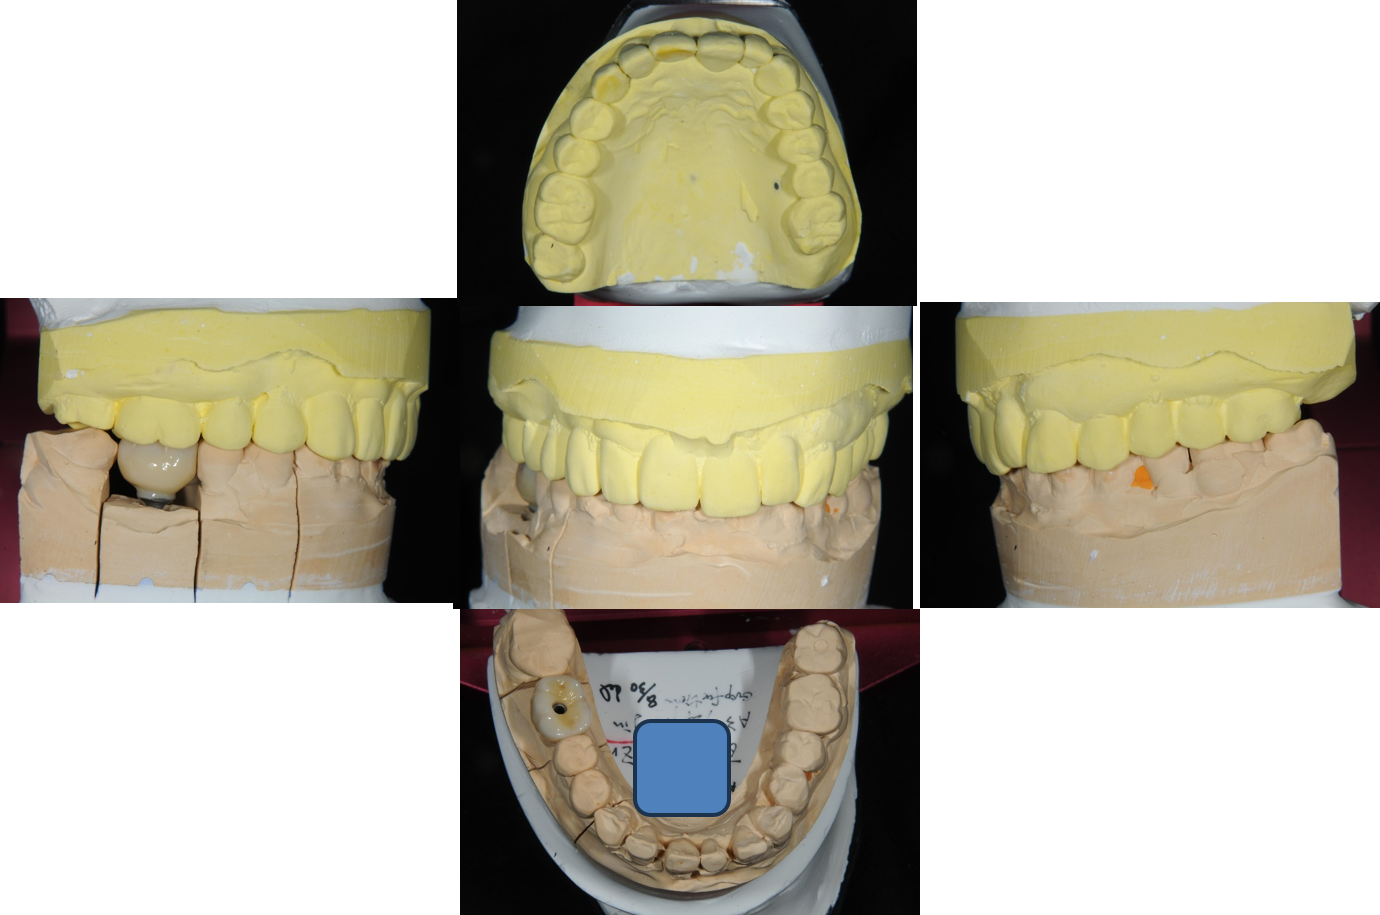

植牙印模與上咬合器